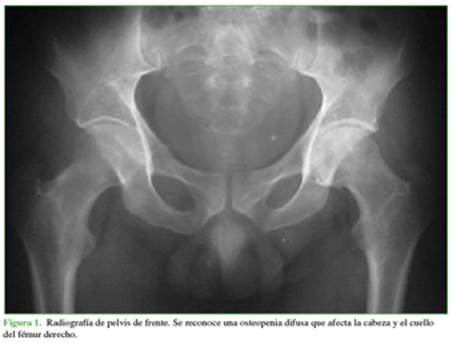

En la radiografía, se reconoce una osteopenia difusa que afecta la cabeza y el cuello femoral derechos (Figura 1).